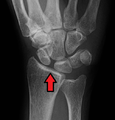

Scapholunate disassociation